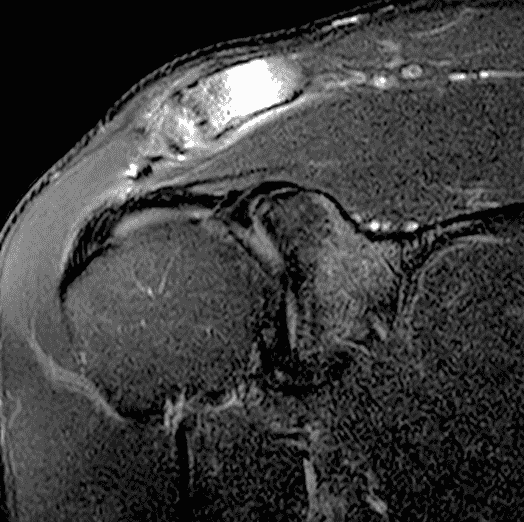

A 49-year-old male, avid weightlifter complains of chronic pain along the superior aspect of his right shoulder. He denies acute trauma. An AP radiograph (Figure 1A), as well as oblique coronal SPAIR (Figure 1B), axial fat-suppressed fluid sensitive (Figure 1C), and oblique sagittal T2-weighted images (Figure 1D) are shown. What are the findings? What is your diagnosis?

MRI: MRI is the primary imaging modality used for the diagnosis of DCO and identifies relevant findings earlier than radiographs or CT.  To differentiate DCO from similar conditions, it is important to identify underlying findings that are isolated to or more pronounced in the distal clavicle compared to other structures.  Osseous changes along both the acromial and distal clavicular margins of the joint often point to a different diagnosis.2

The principle MRI finding of DCO is distal clavicular marrow edema and surrounding inflammation on fluid-sensitive pulse sequences, especially with fat suppression (Figures 3 and 4).2, 9 Marrow changes can occur in patients with normal radiographs,10 in which case a term like “stress/overuse related marrow edema,” might be preferable to “osteolysis.” On MRI, more severe cases may show erosions or cysts in the distal clavicle and loss of the subchondral bone plate in addition to more pronounced marrow and soft tissue edema. A band of low signal paralleling the distal bone end may be present, suggesting a stress fracture line (Figure 5).8 However, a similar appearance can be due to the sclerotic rim surrounding distal clavicle cysts or small erosions (Figure 6). A small effusion or mild synovitis is often present in the AC joint.  Soft tissue edema within and surrounding the AC joint capsule and distal clavicular periosteum may be visible (Figure 3).  Some patients may also show marrow edema (or even erosions) in the anterior acromion, but the changes are typically more severe in the distal clavicle (Figures 5 and 7).2